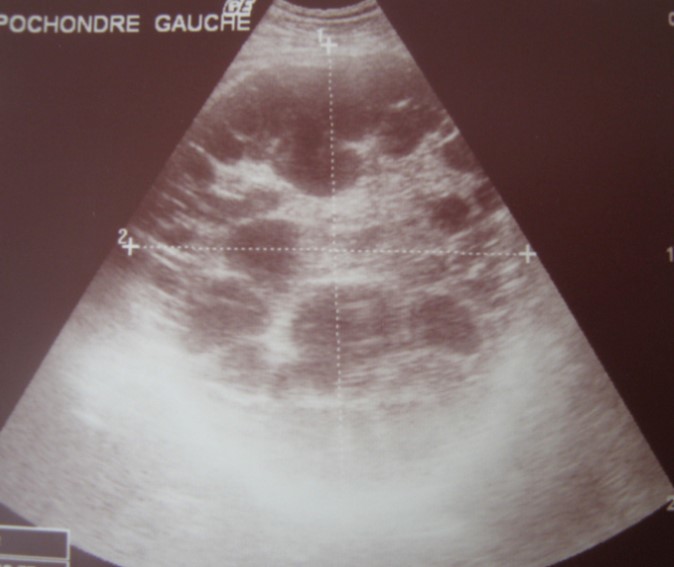

A 17-year-old young man admitted to our department with the complaint of abdominal pain localized in the left upper quadrant for the last 3 months. His physical examination revealed a splenomegaly. Immunoblot assay for Echinococcus was positive. His laboratory tests showed normal results of the serum and urine examinations, No eosinophilia was found. Chest X-ray revealed no pathological signs. An abdominal ultrasonography showed a 20 cm multivesicular cystic mass of spleen (figure 1). Contrast enhanced CT scans detected a huge single 20×16×18cm cystic mass located in the spleen. It had well-defined borders and contained multiple, round, daughter cysts in the periphery of the lesion with calcification (Figure 2, Figure 3, Figure 4). The patient underwent a laparotomy. A large splenic cystic mass was identified, attached to diaphragm, and tail of the pancreas (figure 5). The abdomen was packed with 10% hypertonic saline soaked pads in order to protect peritoneal soilage. A partial cystectomy without splenectomy was performed. Histologic examination of the specimen resection showed an echinococcal organism residing within the hydatid cyst . The patient was discharged after 4 postoperative days. 600 mg per a day of Albendazole therapy was instaured postoperatively and continued for 6 months. Two years after surgery the patient is well with disease free.

Figure 1.Ultrasonography showing a 20 cm multivesicular cystic mass of spleen

Ultrasonography is helpful in detecting Calcification of the cyst wall, presence of daughter cysts, cystic membranes, septa or hydatid sand 10. Lesions are usualy heterogeneous with indistinct margins, showing alveolar appearance. Multiple small round cysts with solid components are frequent. 10, 11.